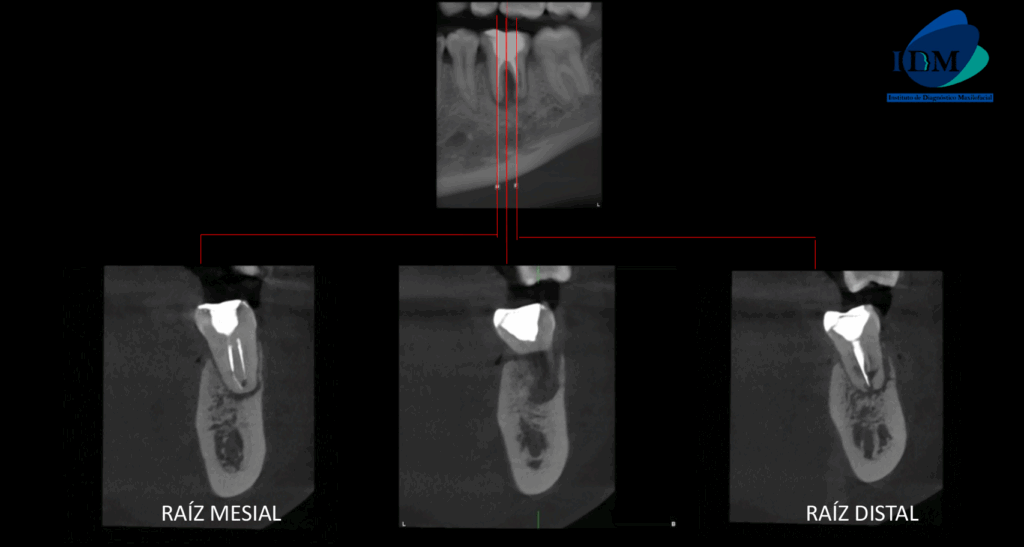

A la evaluación de la tomografía computarizada se puede observar el tratamiento de conductos de ambas raíces, sim embargo el conducto distal presenta una obturación orientada hacia la superficie interna a nivel de tercio medio radicular (vista en cortes axiales), asimismo observamos en cortes tangenciales la reabsorción radicular externa de la raíz distal que compromete el tercio medio y apical. La raíz mesial presenta reabsorción radicular externa de tercio apical. Finalmente se evidencia compromiso de la tabla ósea lingual (cortes transaxiales) y osteítis condensante circundante.

RECONSTRUCCIÓN 3D